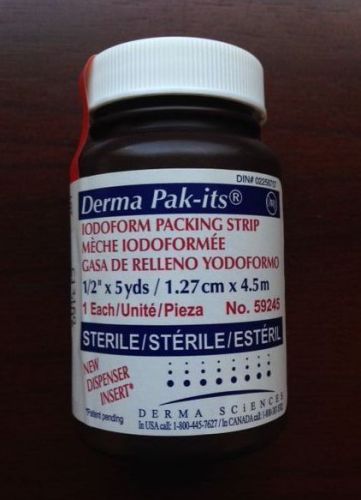

Derma Sciences Iodoform Gauze Packing Strips 1/2"x15' #59245 Sterile Pak-its